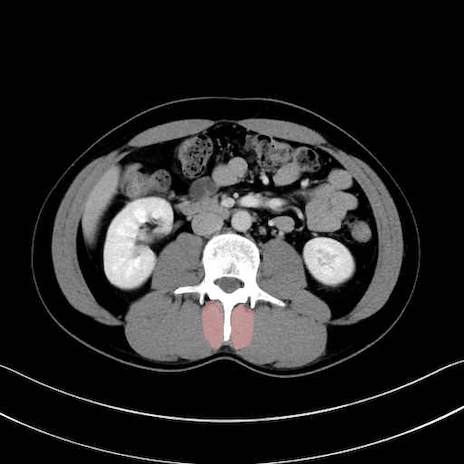

多裂筋 (Multifidus)